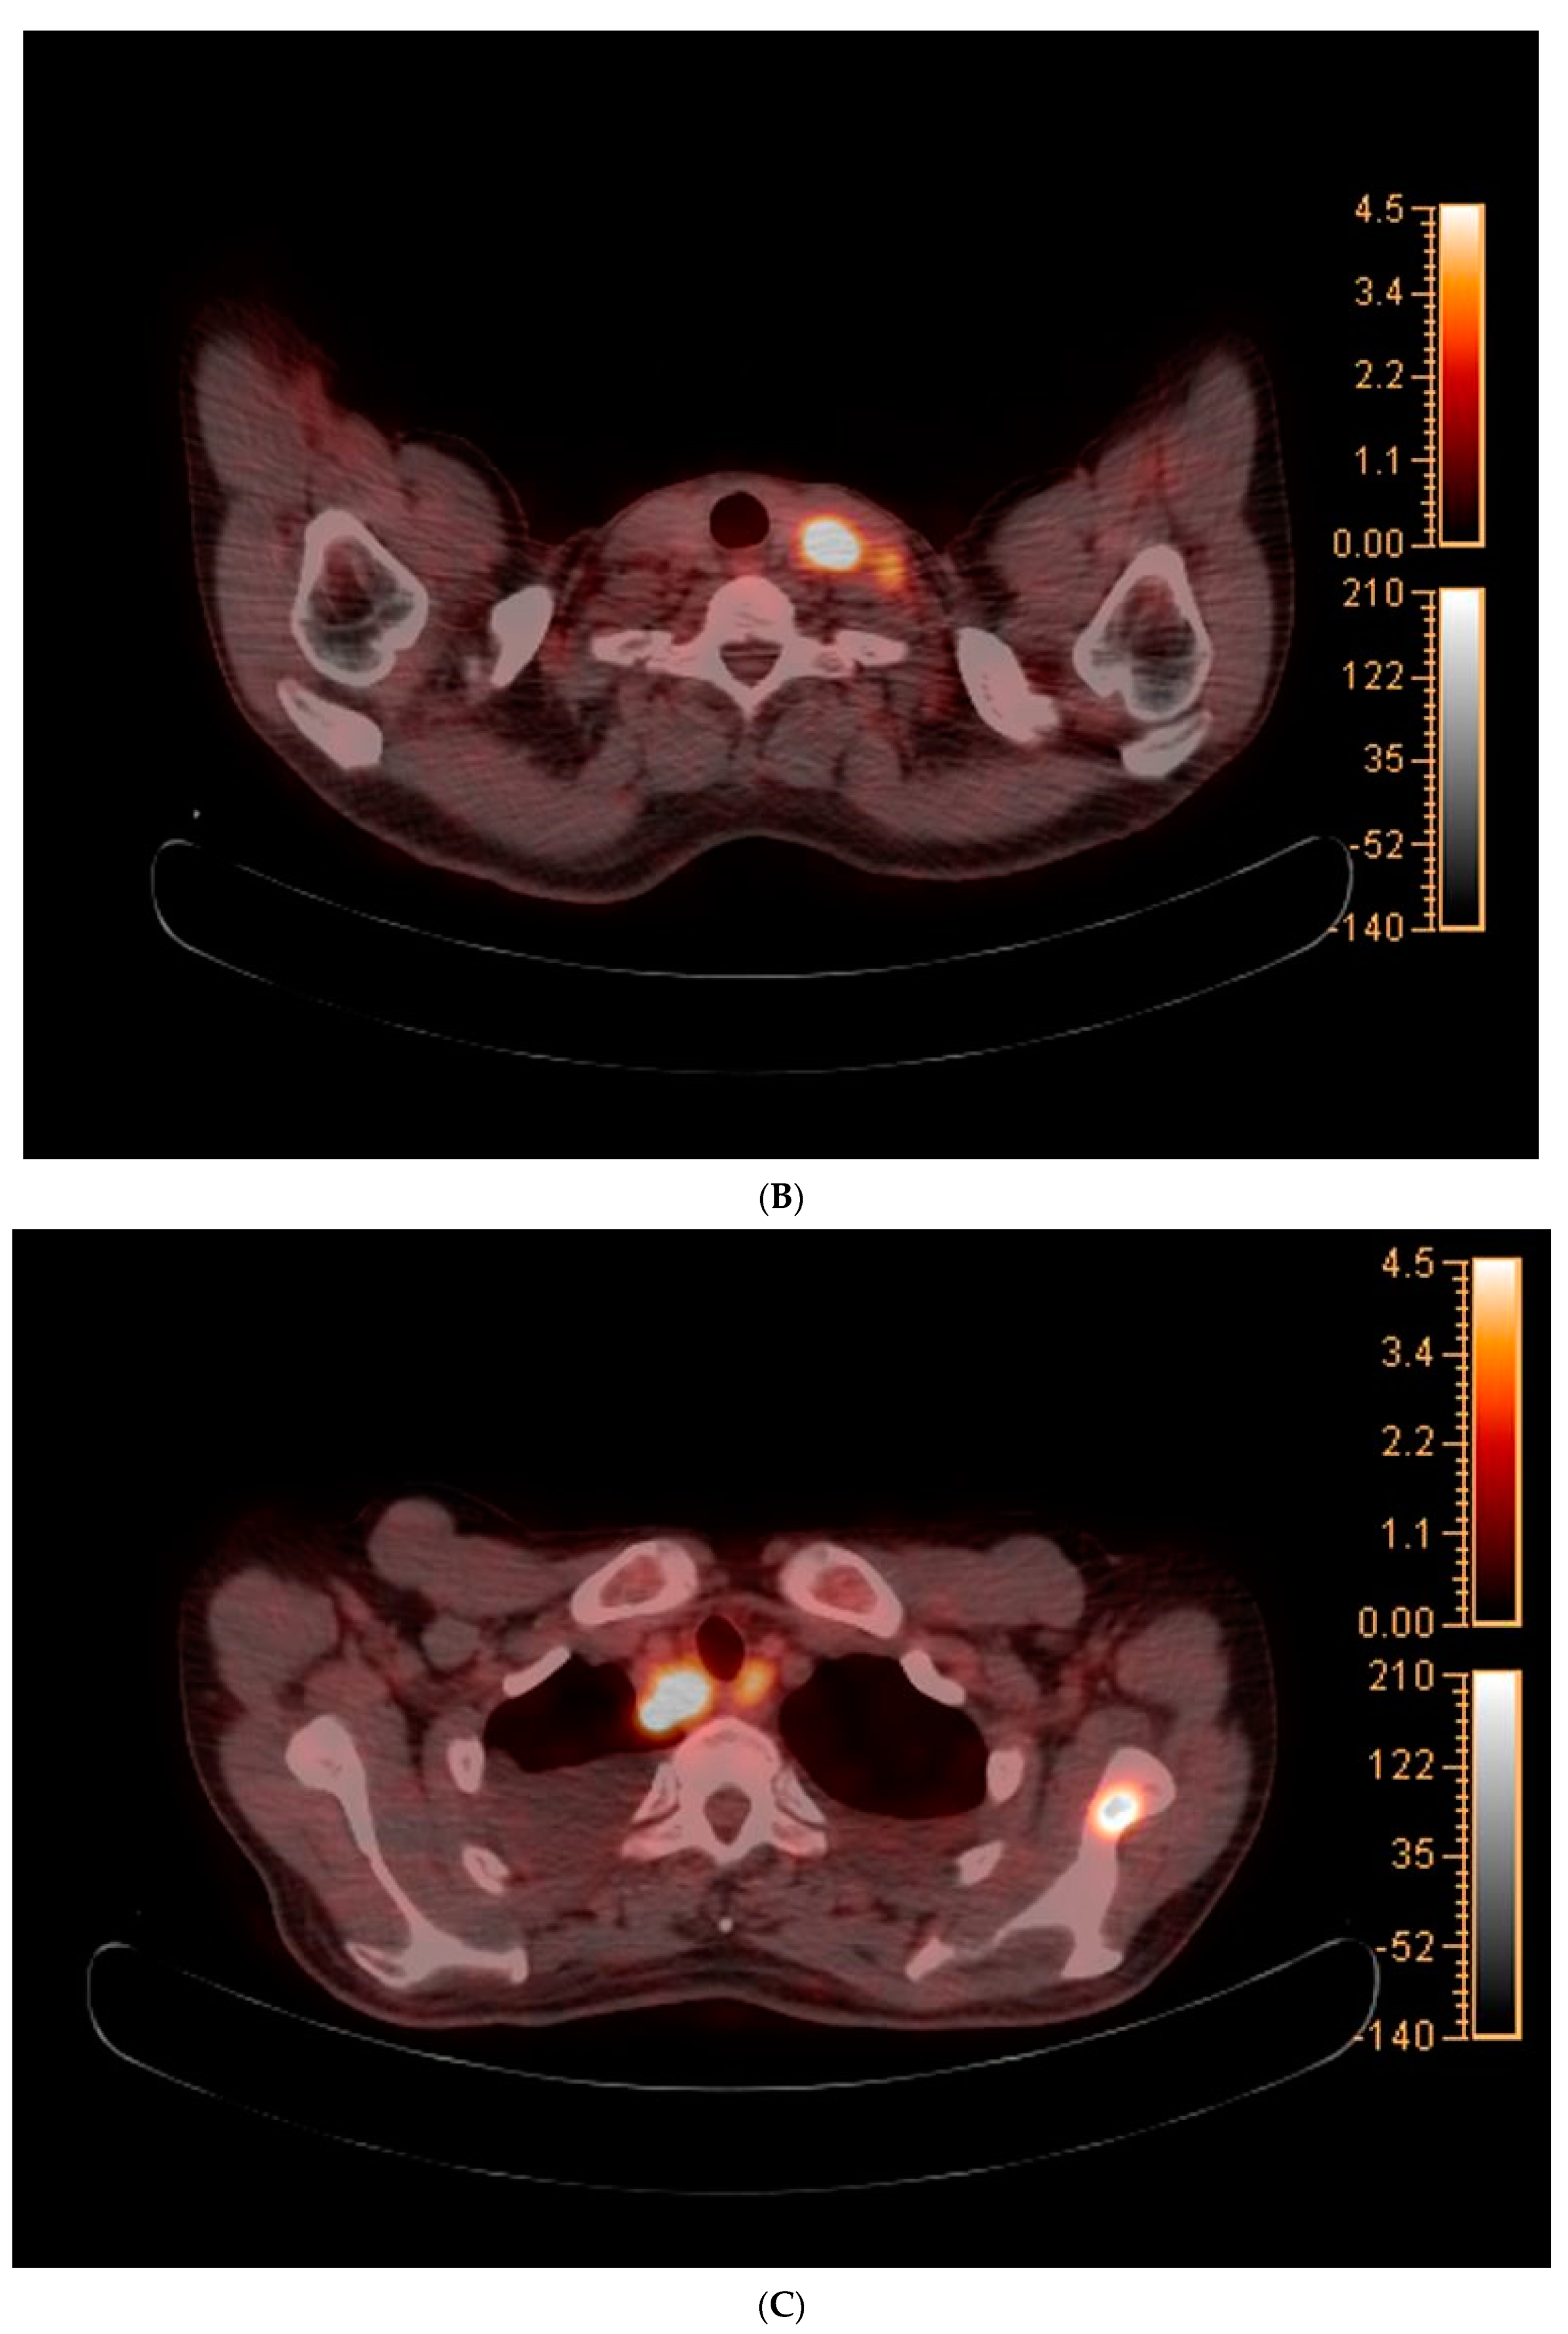

2. Case Report